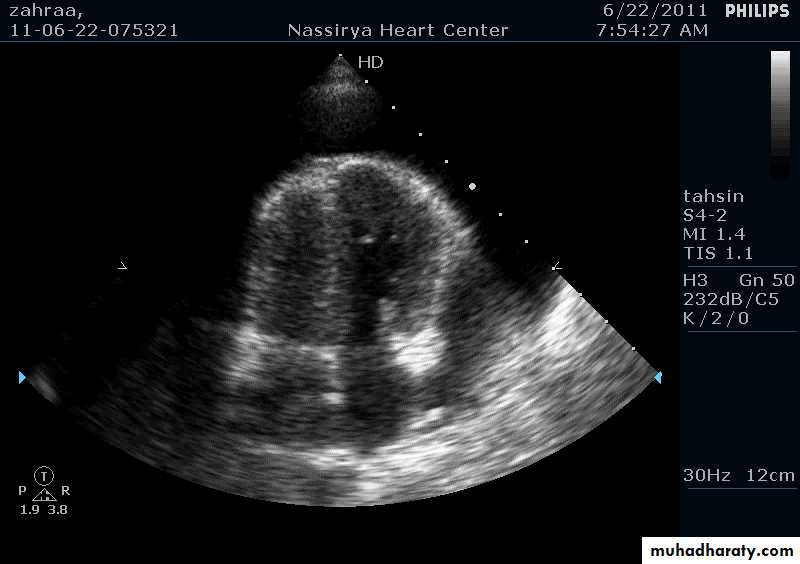

Echocardiography & Doppler:RA & LA enlargement

Normal size ventricles

Pericardial thickening

CT/MRI: demonstrate the thickened pericardium

Cardiac catheterization: equalization of diastolic pressures in all 4 cardiac chambers